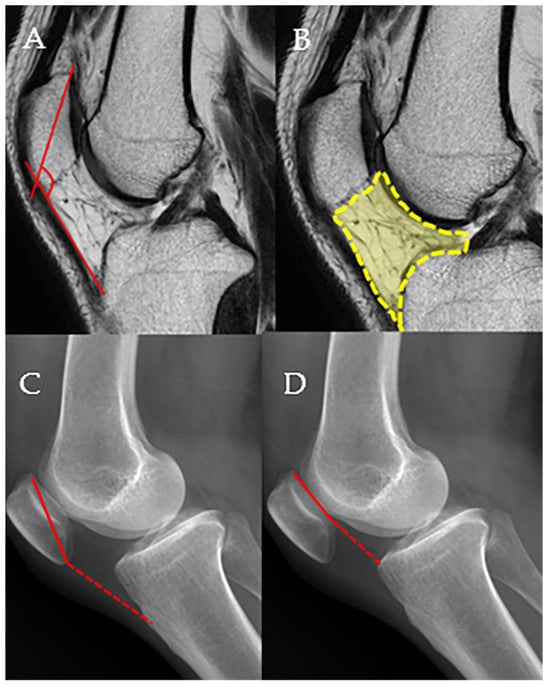

Before surgery and during follow-up, MRI, weight-bearing whole leg AP radiograph, standing knee antero-posterior (AP), standing knee postero-anterior 45°, knee lateral views of radiographic images, and non-weight-bearing Merchant view of patellofemoral joint were obtained. Magnetic resonance imaging was conducted using either 1.5-Tesla or 3.0-Tesla high-field superconducting scanners. All patients underwent MRI without a contrast agent with the knee in full extension while in the supine position. All MRI and plain radiographic measurements were made on a picture archiving and communication system workstation (Maroview, version 5.4.10.52; Marotech, Seoul, Republic of Korea) by two of the authors (P.Y.C, K.Y.M), who are both experienced orthopedists. Measurements were performed twice by each of the two authors. The patella–patellar tendon angle (PPTA) and infrapatellar fat pad volume (IPFV) were measured on MRI [3], and Insall–Salvati ratio (ISR), Caton–Deschamp index (CDI), and the degree of arthritis in patella-femoral compartment were measured on simple radiographs [22,23] (Figure 2). The PPTA was evaluated on T1-weighted midsagittal images to analyze the sagittal patellar alignment of the patella-femoral joint (PFJ). The PPTA was defined as the angle between the line joining the upper and lower patellar poles and the line through the mid-portion of the patellar tendon [3]. The infrapatellar fat pad (IPFP) lies within the joint capsule but outside the synovial lining, bordered anteriorly by the patellar tendon and posteriorly by the synovial membrane of the femorotibial joint. Superiorly, it connects to the inferior pole of the patella and extends posteriorly toward the intercondylar notch through two alar folds, which merge to form the infrapatellar plica. It is situated adjacent to the femoral trochlear cartilage in the superoposterior region. To calculate its area, the IPFP was outlined manually on sagittal T2-weighted MRI slices at the level showing the greatest cross-sectional dimension [3]. The Insall–Salvati index was calculated as the ratio of the length of the longitudinal patellar diameter to the length of the line connecting the most inferior point of the patella to the patellar insertion site on the tibial tuberosity [22]. In the sagittal plane, the Caton–Deschamps index was calculated as the ratio of the length of the retropatellar surface to the length of the line connecting the most inferior point of the patella to the retropatellar surface of the tibial plateau [22].

Figure 2.

The measurement methods for the patella–patellar tendon angle (PPTA), infrapatellar fat pad volume (IPFV), Insall–Salvati ratio (ISR), and Caton–Deschamps index (CDI) are described. The procedures for PPTA and IPFV measurements are detailed in the main text. (A) PPTA, (B) IPFV, (C) ISR, the ratio of the dashed line to the solid line, (D). CDI, the ratio of the dashed line to the solid line.